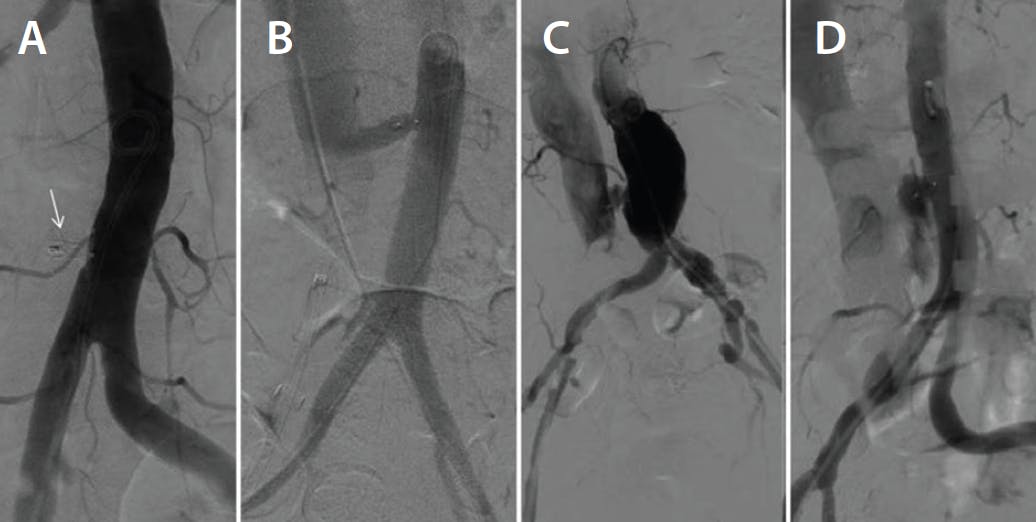

First, heparin is fully reversed with protamine. The aortic pigtail catheter is withdrawn to just below the transcaval crossing location. Through an 8.5-F Agilis NXT SML Curl sheath, a 10/8 Amplatzer Duct Occluder 1 is deployed by first withdrawing the TAVR sheath back into the IVC, carefully positioning the aortic disc of the occluder against the aortic wall, and then passively releasing the neck of the occluder in the aortocaval tract. A brief drop in blood pressure is commonly observed but is usually tolerated. Pressors that would raise arterial pressure to suprasystemic levels should be avoided. Digital subtraction angiography using 10 mL at 10 mL/sec is then performed. There are four angiographic patterns of closure: type 0, complete occlusion; type 1, patent fistula with a tunnel around the occluder; type 2, patent fistula with a cruciform appearance (the most common); and type 3, extravasation (Figure 2). If the patient remains hemodynamically stable with a closure pattern of 0, 1, or 2, the large-bore femoral venous access is closed using the “preclose” technique, figure-of-eight suture, or manual pressure. Figure 3 summarizes key steps of the transcaval technique.

Figure 2. Transcaval closure patterns. There are four angiographic patterns of closure: complete occlusion around the closure device (white arrow) (A); patent fistula with a tunnel around the occluder (B); patent fistula with a “cruciform” appearance (C); and extravasation (D). Reproduced with permission from Lederman RJ et al. How to perform transcaval access and closure for transcatheter aortic valve implantation. Catheter Cardiovasc Interv. 2015;86:1242-1254.